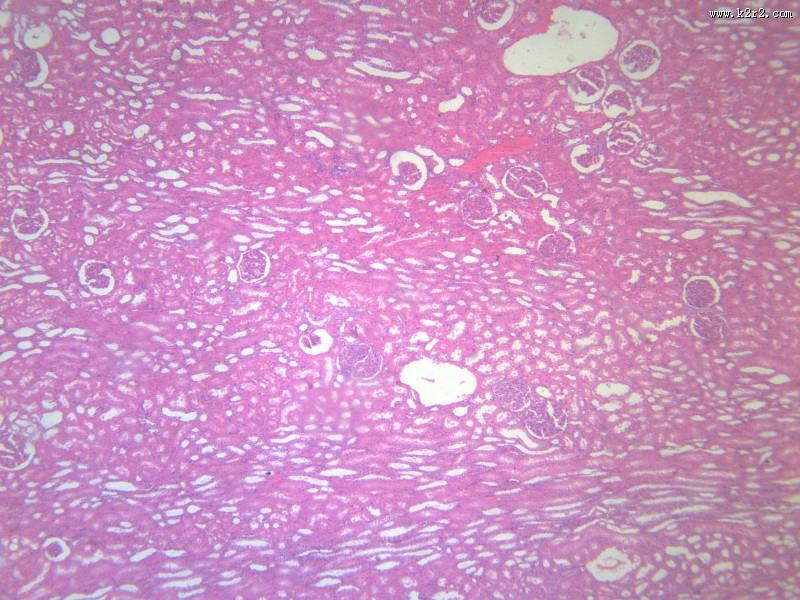

肾小管水肿 - 第1张

肾小管水肿

图集中 / 共有 11 张图片

肾小管坏死

肺水肿

医学

显微切片

水肿